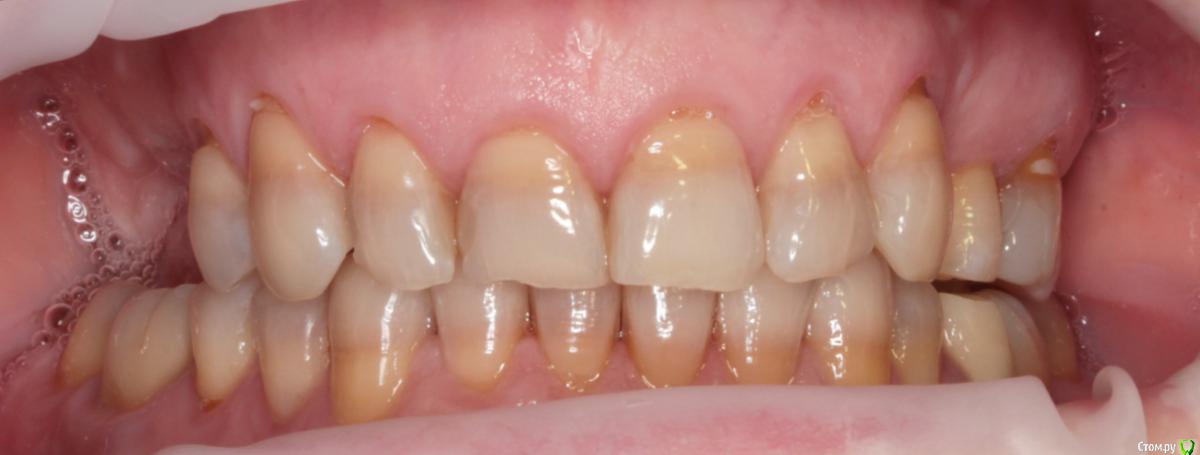

Пациентка пришла с целью восстановления отсутствующих 15,16,17,24,27 з.

Из анамнеза - хронический двухсторонний синусит, соответствующие зубы удалены более 5-ти лет назад, тетрациклиновые зубы ( от изменения цвета отказалась ).

это времянки, постоянная - средний ряд, правая сторона, последнее фото